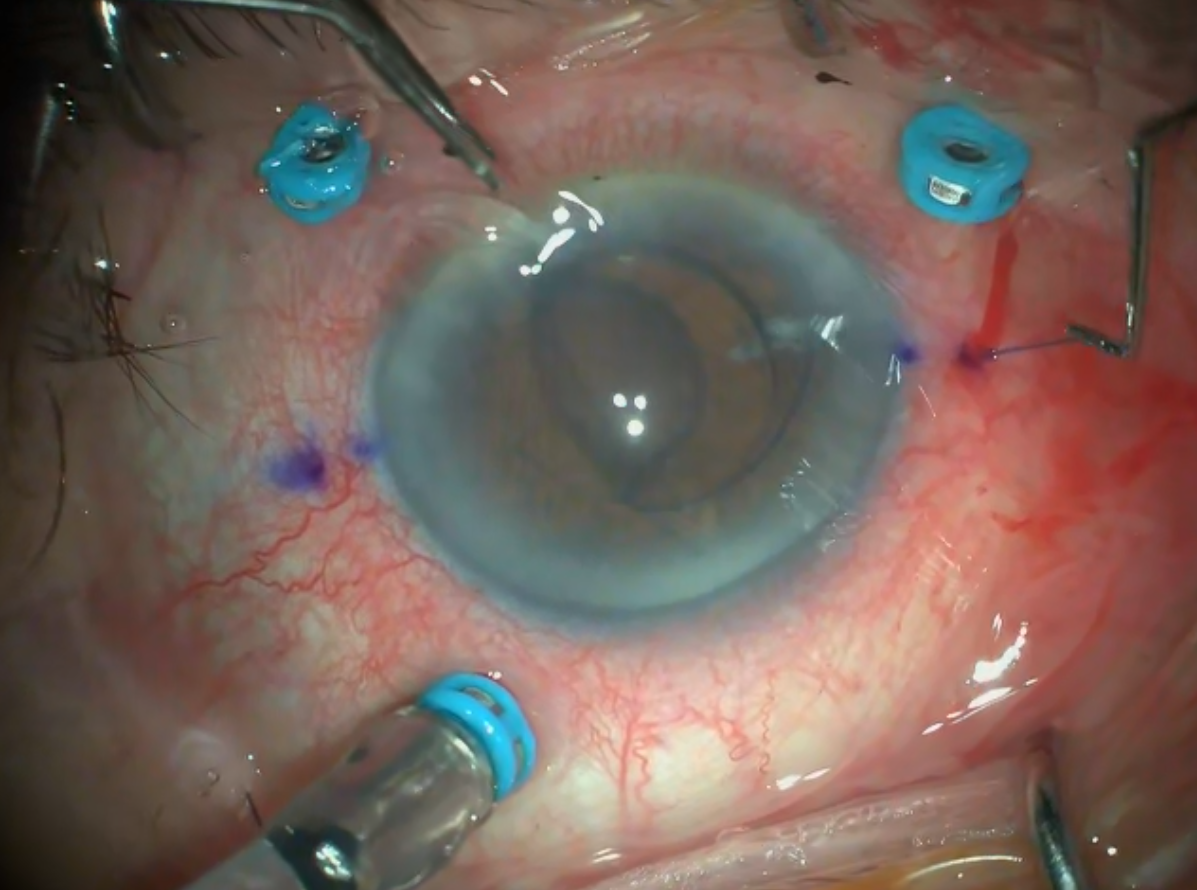

2026 Şubat Ayın Videosu

Retina dekolmanı cerrahisi sırasında perflorokarbon sıvı uygulaması esnasında ge ...